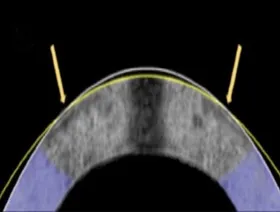

وتتميز القرنية المطبوعة بكثافة خلايا عالية، وشفافية بيولوجية، وثبات ميكانيكي يُسهّل عملية الزراعة، وعلاوة على ذلك، وخلافًا للقرنية المزروعة من التبرعات البشرية، فإن القرنية المطبوعة خالية تمامًا من التلوث، وتُختبر بعناية في مختبرات الشركة، بحسب بيان للشركة.